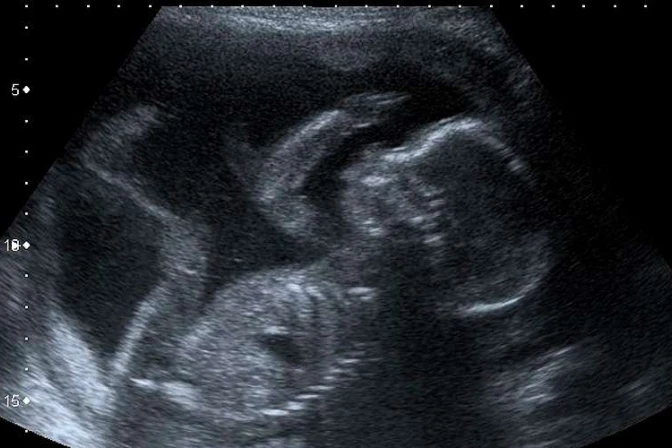

Un estudio de la University College London descubrió que los golpes que dan los bebés dentro del vientre materno, entre estos las patadas, y otros movimientos, les ayudan a desarrollar su cerebro y reconocer las partes de su cuerpo.

Según indicó LiveSciense, el estudio sugiere que con cada golpe o patada –conocidas como movimientos fetales– el bebé construye una red cerebral básica que le permite entender qué parte del cuerpo se está moviendo y cómo se toca.